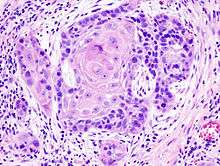

Microscopic appearance

One method of classifying squamous cell carcinomas is by their appearance under microscope. Subtypes may include:

- Adenoid squamous cell carcinoma' (also known as "Pseudoglandular squamous cell carcinoma"), characterized by a tubular microscopic pattern and keratinocyte acantholysis.[22]

- Basaloid squamous cell carcinoma is characterized by a predilection for the tongue base.[22]

- Clear-cell squamous cell carcinoma (also known as "Clear-cell carcinoma of the skin") is characterized by keratinocytes that appear clear as a result of hydropic swelling.[22]

- Signet-ring-cell squamous cell carcinoma (occasionally rendered as "signet-ring-cell squamous cell carcinoma") is a histological variant characterized by concentric rings composed of keratin and large vacuoles corresponding to markedly dilated endoplasmic reticulum.[22] These vacuoles grow to such an extent that they radically displace the cell nucleus toward the cell membrane, giving the cell a distinctive superficial resemblance to a "signet ring" when viewed under a microscope.

- Spindle-cell squamous cell carcinoma (also known as "Spindle-cell carcinoma"[23]) is a subtype characterized by spindle-shaped atypical cells.[22]

SCC is a histologically distinct form of cancer. It arises from the uncontrolled multiplication of cells of epithelium, or cells showing particular cytological or tissue architectural characteristics of squamous cell differentiation, such as the presence of keratin, tonofilament bundles, or desmosomes, structures involved in cell-to-cell adhesion.